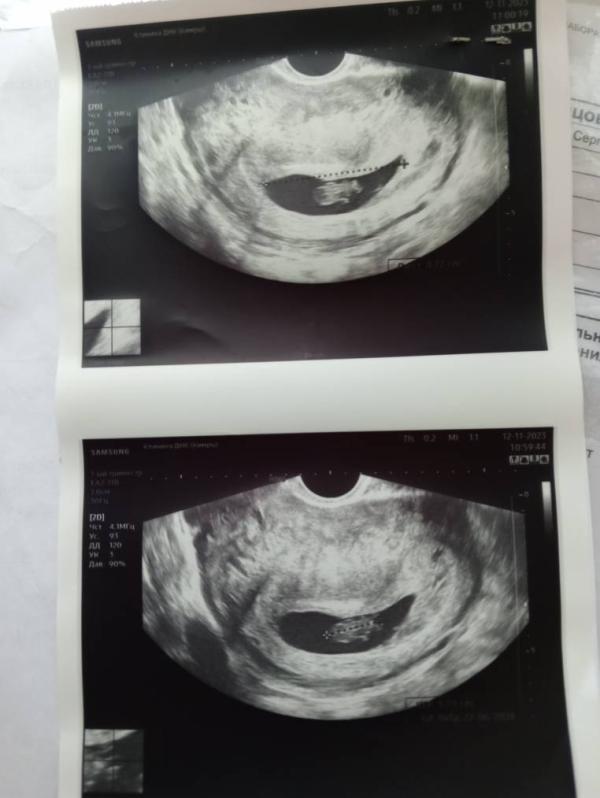

Новости с полей.. Мой шок в шоке. Внимание!!! ВРАЧИ ПЕРЕПУТАЛИ и посчитали, что желточный мешок - это второй ребенок😅🤷🤷 Как так можно, это просто жесть! Малыш здоров и активен, срок 8н1д. Привыкаю отвыкать, отвыкаю привыкать😅😅😅 Я уже была готова к двойне, теперь вот заново привыкаю к тому, что малыш один💞